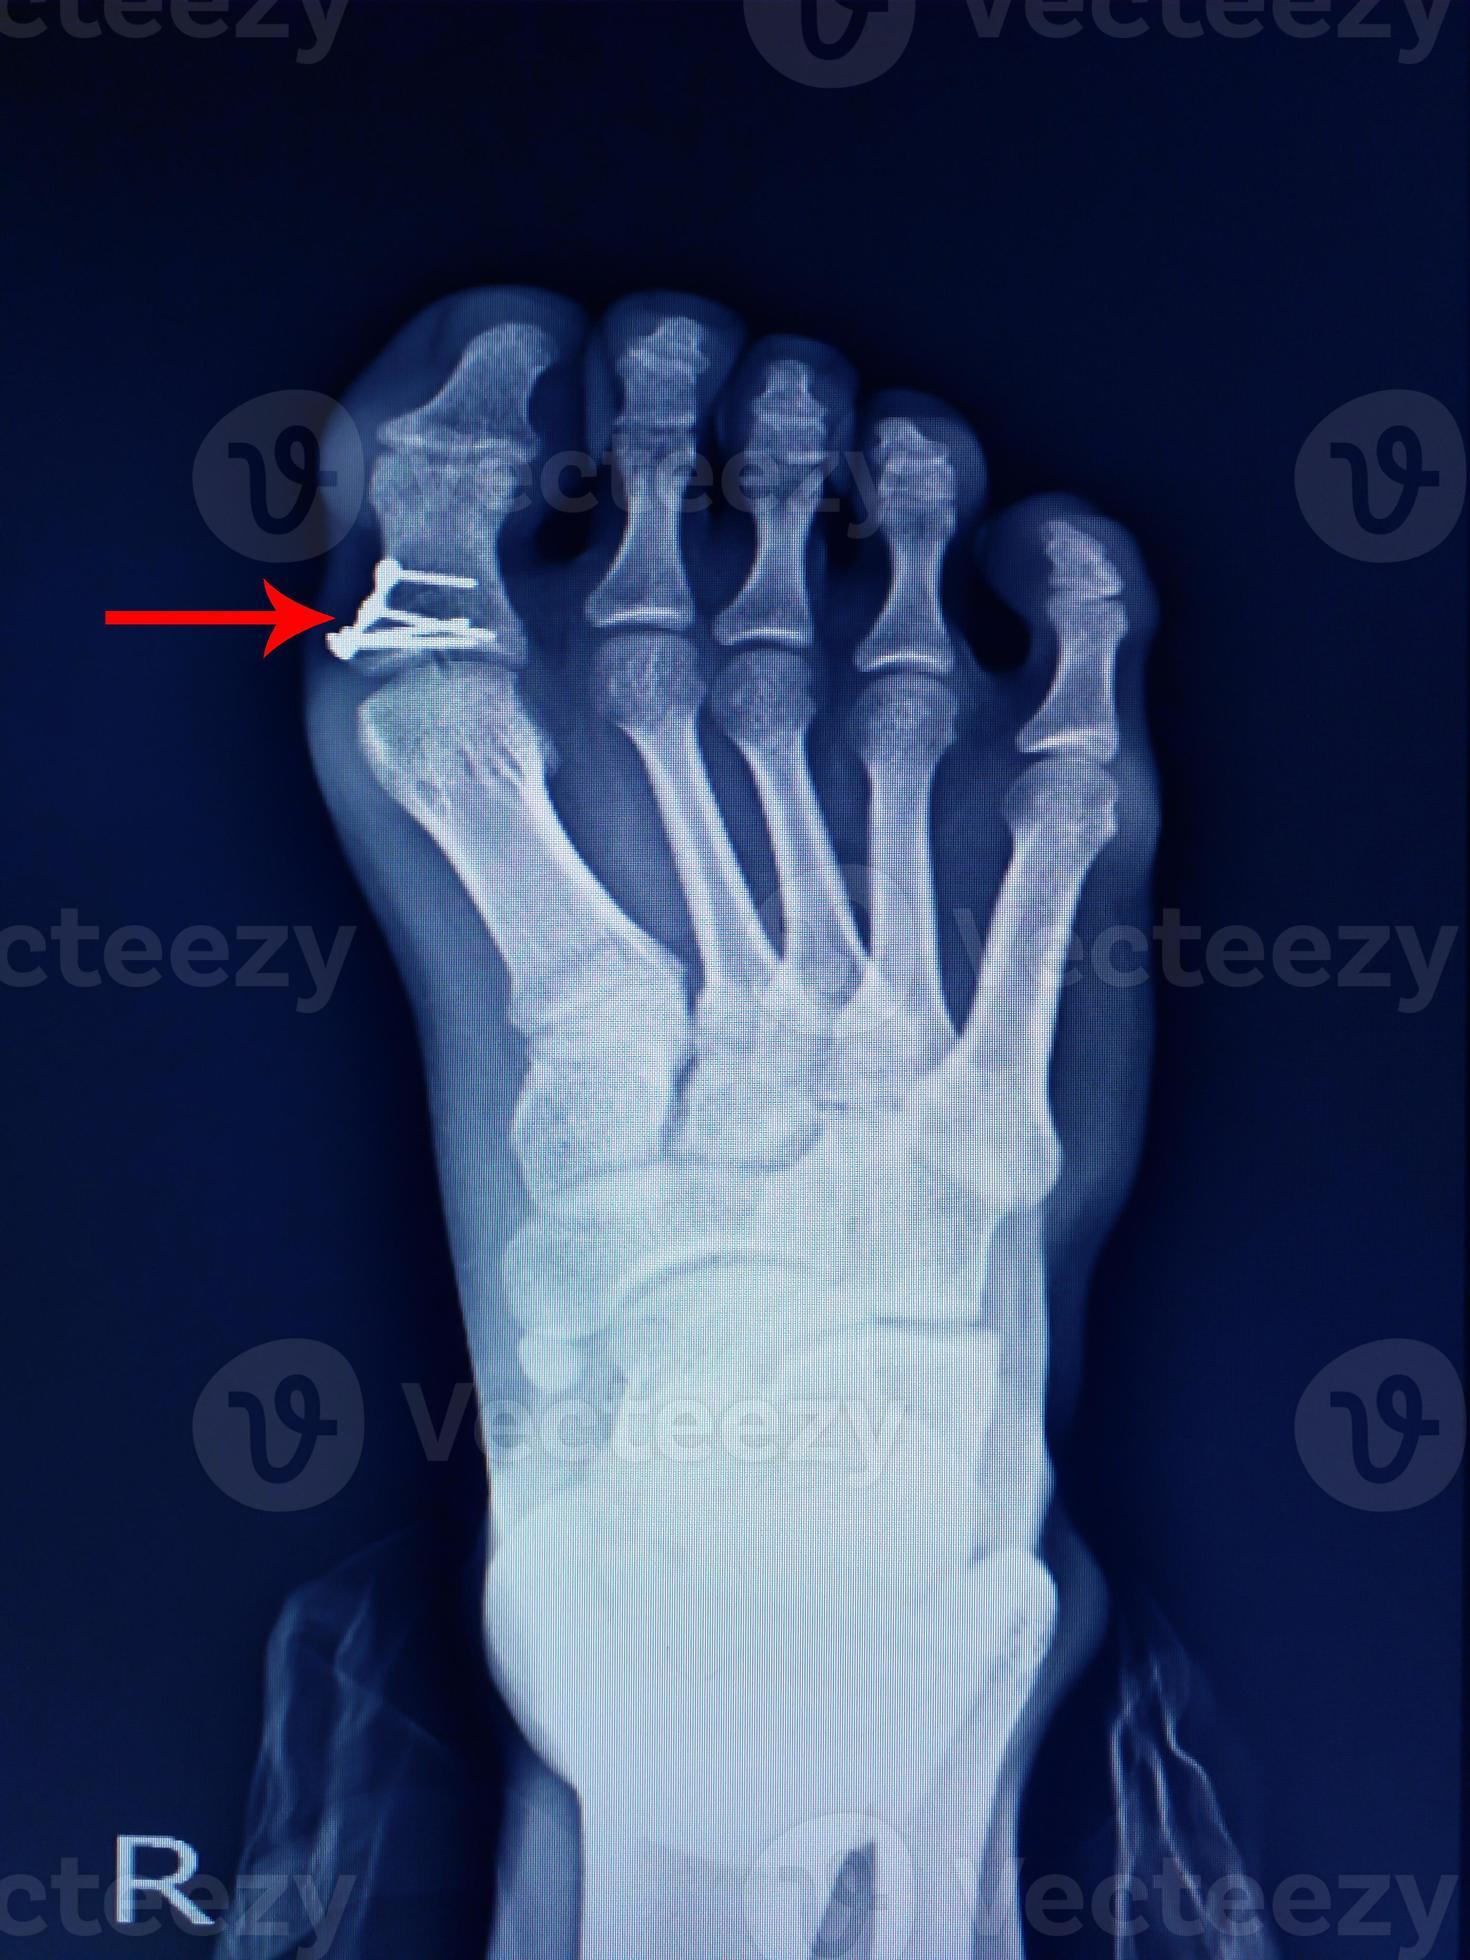

From www.vecteezy.com

xray foot fracture proximal phalang and surgery fix mini plate and Foot Fracture Definition They most often involve the metatarsals and. Foot fractures are among the most common foot injuries evaluated by primary care physicians. Fractures of the ankle joint are common amongst adults. The midfoot is the area of your foot that makes up the arch,. A broken foot, or foot fracture, is a common injury that can occur in any of the. Foot Fracture Definition.